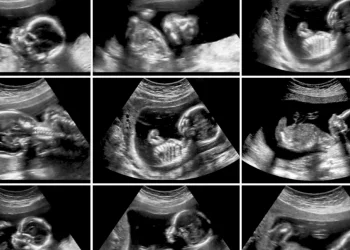

הרופא הביט במסך האולטרסאונד, כיוון עוד פעם את המתמר - ונשאר המום. אחרי רגע קצר של שתיקה, הוא בישר לה בעדינות: "את נושאת ברחמך תשעה עוברים." כן, תשעה. לא טעות, לא כפל - אלא תשיעייה של ממש.

המקרה, מן הנדירים שנראו ברפואה המודרנית, עורר מיד עניין ציבורי אדיר במצרים. כלי תקשורת במדינה דיווחו בהרחבה, ורופאים בכירים התראיינו והסבירו את הסיכון הבריאותי והמורכבות שכרוכים בהריון שכזה.